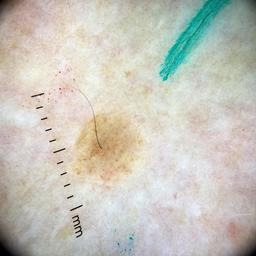

ISIC_4949599

Clinical

Field Value

acquisition_day 216

age_approx 75

anatom_site_1 Lower extremity

anatom_site_general lower extremity

concomitant_biopsy False

diagnosis_1 Benign

diagnosis_confirm_type single image expert consensus

family_hx_mm True

image_manipulation instrument only

image_type dermoscopic

lesion_id IL_7554877

patient_id IP_4319298

personal_hx_mm True

sex female